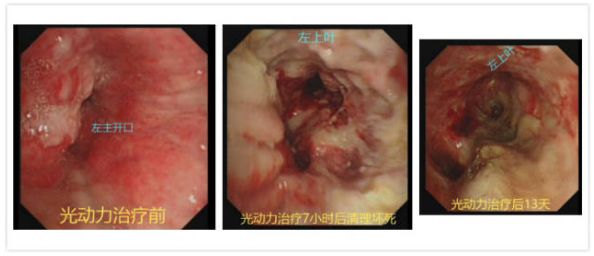

内镜下,患者左主支气管完全堵塞,表面新生物糜烂出血,经超声支气管镜很快取得活检组织。为了尽快切除肿瘤,恢复气管通畅,冯起校团队运用氩气刀、电凝、冷冻等方法进行消融,但患者左主支气管开口新生物血运非常丰富,一触碰就会出血,需要及时止血,手术近2个小时左主支气管管腔依然不通。

为争取救治时机,经与家属详细沟通获得同意后,当天晚上,冯起校主任为谢大爷注射血卟啉注射液(光敏剂),做好施行支气管镜及内科胸腔镜的光动力治疗手术的准备,于4月30日顺利完成了手术。

光动力治疗7小时后,冯主任为谢大爷清理坏死组织,发现左肺固有上叶及舌叶支气管管腔复通,患者呼吸困难症状明显好转,血氧由85%回升至99%,终于渡过了危险期。

同日,活检病理结果回报低分化鳞癌,谢大爷随即接受了全身抗肿瘤治疗。用药后患者自我感觉一天比一天好,左侧胸腔积液消失,复查胸部CT左肺复张,气管镜下左上叶支气管黏膜逐渐修复,左下叶管腔部分复通,谢大爷现可下地缓慢步行,生活质量明显提高。

光动力治疗诱导肿瘤组织凋亡。